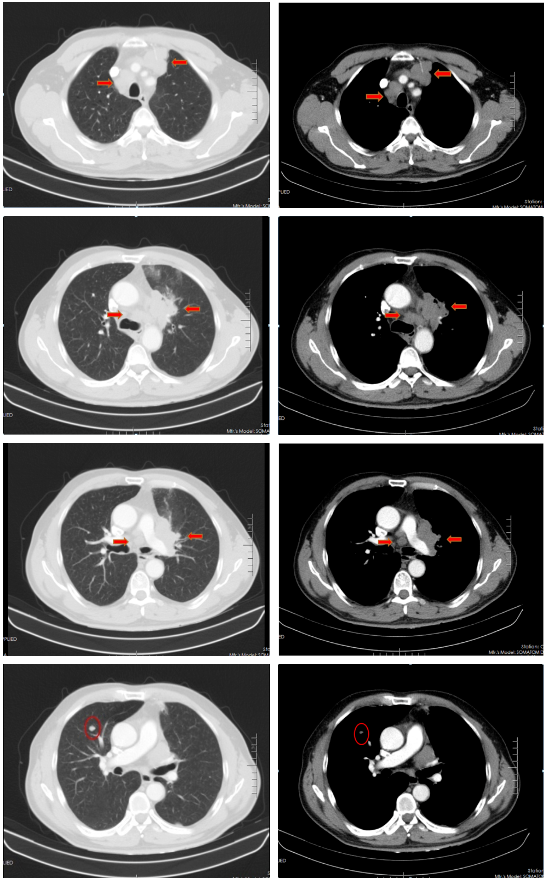

胸部增强CT(2022-02-12):左肺门及纵隔内见团块状软组织密度影,大小约62mm×42mm,边界不规整,内见血管影穿行,增强扫描呈轻度强化,局部支气管狭窄,远端肺内见片状磨玻璃密度影,边界欠清。右肺上叶见结节状密度增高影,较大直径约为8mm,增强扫描呈轻中度强化,右侧斜裂见长径约为6mm的高密度影,增强扫描未见明显强化;两肺透亮度增强,左肺下叶胸膜下囊状透光区。余气管、支气管通畅,未见明显狭窄、阻塞。纵隔和左肺门区见多发肿大淋巴结影,部分融合。两侧胸腔无明显积液。胸部CT诊断:左肺门及纵隔内占位,考虑肺Ca;纵隔及左肺门淋巴结肿大;右肺上叶结节,转移可能;右侧斜裂下结节;两肺肺气肿、左肺下叶肺大泡。

胸部CT(2022-04-12):左肺门及纵隔内见团块状软组织密度影,大小约57mm×37mm,边界不规整,局部支气管狭窄,远端肺内见片状磨玻璃密度影,边界欠清。右肺上叶见结节状密度增高影,较大直径约为9mm,右侧斜裂见长径约为7mm的高密度影;两肺透亮度增强,左肺下叶胸膜下囊状透光区;两肺可见索条状影。余气管、支气管通畅,未见明显狭窄、阻塞。纵隔和左肺门区见多发肿大淋巴结影,部分融合。两侧胸腔无明显积液。胸部CT诊断:左肺占位复查;纵隔及左肺门淋巴结肿大;右肺上叶结节,转移可能;右侧斜裂下结节;两肺肺气肿、左肺下叶肺大泡。

治疗后评价:经过EP方案治疗后两周期,患者仍有咳嗽、咳痰及左侧胸痛,症状无缓解,且出现体重下降;影像学检查提示左肺病灶及纵膈淋巴结及肺门淋巴结较前缩小不明显(缩小<30%),疗效评价SD。总体效果欠佳。

胸部CT(2022-07-15):双侧肺野透亮度增加,以两上肺和胸膜下明显。双肺纹理增多、增粗,紊乱,左肺上叶条片状高密度灶,大小约45mm×19mm,小叶间隔增厚。气管、左右主支气管无明显狭窄。纵隔内未见肿大淋巴结影。两侧胸腔无明显积液。胸部CT诊断:左上肺门占位复查;慢性支气管炎-肺气肿样改变。

治疗后评价:患者经过EP方案联合斯鲁利单抗治疗四周期后,患者咳嗽、咳痰及左侧胸痛症状消失,体重逐渐恢复;影像学提示左肺病灶及纵膈淋巴结及肺门淋巴结较前明显缩小(缩小>30%),右肺结节基本消失;疗效评价:PR(接近CR)。

胸部CT(2022-08-30):双侧肺野透亮度增加,以两上肺和胸膜下明显。双肺纹理增多、增粗,紊乱,左肺上叶见条片状高密度灶,大小29mm×18mm,小叶间隔增厚,两肺下叶见囊状透亮区。气管、左右主支气管无明显狭窄。纵隔内未见肿大淋巴结影。两侧胸腔无明显积液。胸部CT诊断:左上肺门占位复查;慢性支气管炎-肺气肿样改变;两肺下叶肺气肿。

治疗后评价:患者经过斯鲁利单抗单药维持治疗两周期后,患者未再出现咳嗽等症状,体重逐渐增加。影像学提示左肺病灶及纵隔淋巴结及肺门淋巴结、右肺结节基本消失,疗效评价接近CR。